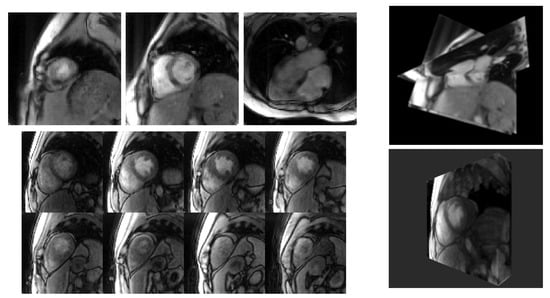

3. Results